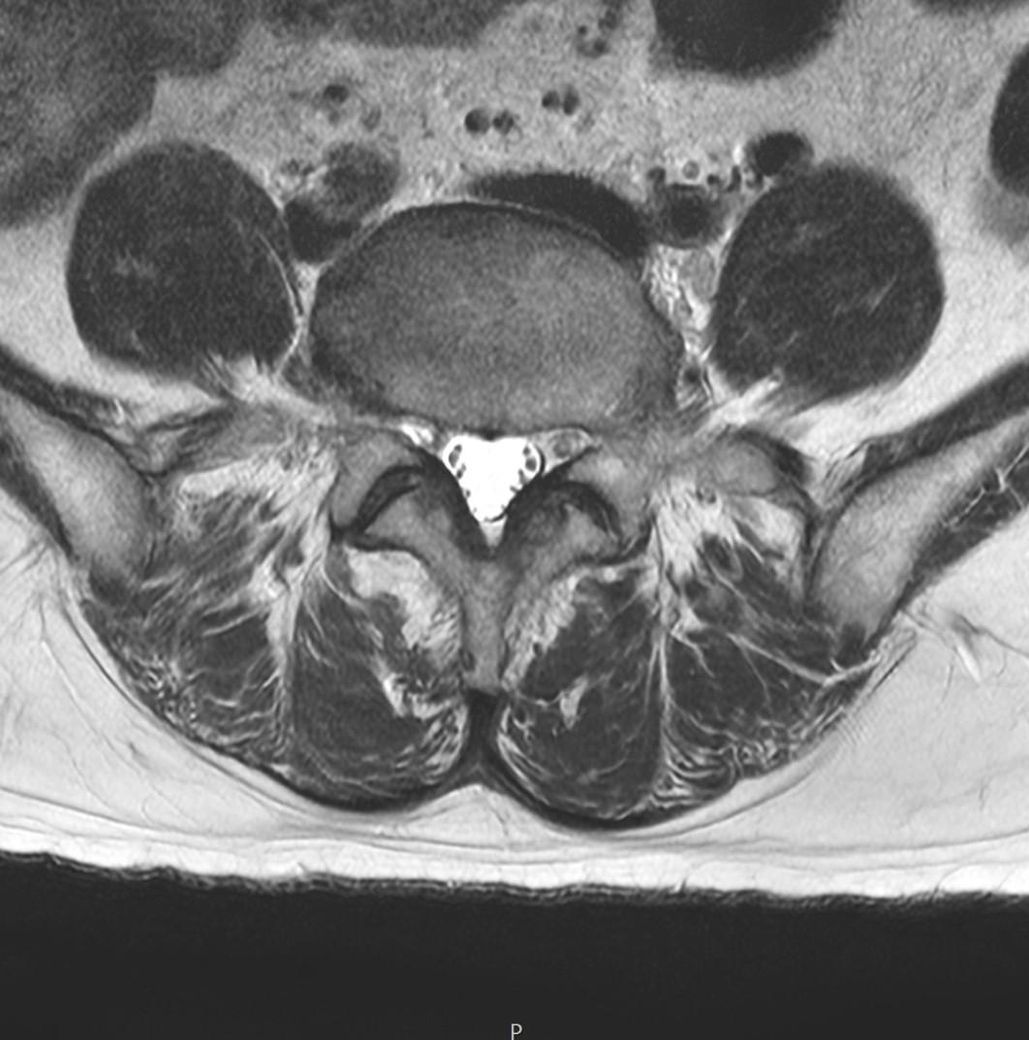

이거 디스크 맞나요? MRI 이미지있어요.

촬영한 이미지에요.

어느 위치인지 몰라요.

가운데 동그라미가 디스크라고 들었어요.

이미지의 오른쪽 아래가 퍼진것처럼 보여요.

혹시 터진 건 아니겠죠?

근육도 괜찮은지 봐주시면 감사하겠습니다.

디스크돌출 여부나 터짐을 확인하려면 전문의가 직접 mri영상을 확인하고 진단을 내려야 합니다. 근육 상태나 다른 이상이 있는지도 확인이 필요하므로 정형외과나 신경외과 전문의에게 mri결과를 가져가 상담을 받는 것이 좋아요!

공유해주신 사진상 정확한 상태를 확인하기는 어려우나 디스크의 큰 문제는 없는 것으로 보이며 자세한 진단 같은 경우 병원에 방문하시어 판독 받아보시는게 좋을 것으로 생각됩니다.

질문자분께서 첨부해주신 영상에서는 크게 신경 주변에 압박이 관찰되지는 않는데요, 이외에 통증이나 불편감이 느껴지시는 경우에는 치료가 필요할 수 있으므로, 전문의에게 진료를 통해 적절한 치료를 받아보시는 방법을 추천드립니다.